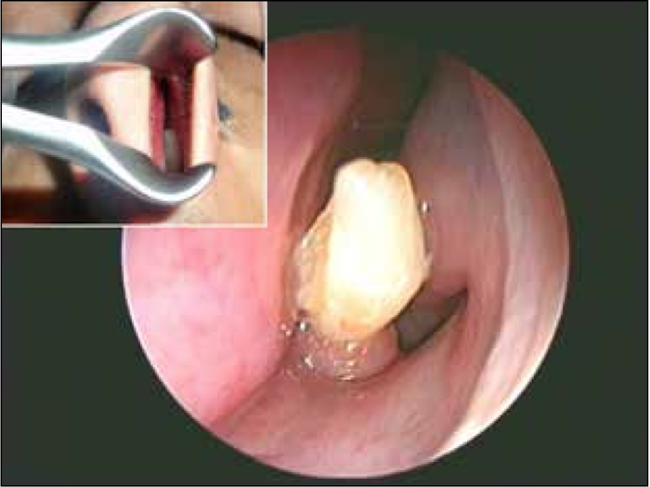

ΦΩΤΟ-«Φύτρωσε» δόντι στη μύτη του

Δεν πίστευαν στα μάτια τους οι γιατροί στη Σαουδική Αραβία όταν είδαν στη μύτη ενός 22χρονου να έχει φυτρώσει ένα δόντι.

Όταν, πλέον, αποφάσισε να επισκεφθεί τον γιατρό έμεινε με το στόμα ανοιχτό. Ένα δόντι είχε φυτρώσει και μεγάλωνε καθημερινά με αποτέλεσμα να «τρώει» το δέρμα και να προκαλεί την αιμορραγία.

Τελικά ο 22χρονος υπεβλήθη σε επέμβαση και το πρόβλημά του λύθηκε. Έχασε, βέβαια, ένα δόντι…

Δείτε τις φωτογραφίες